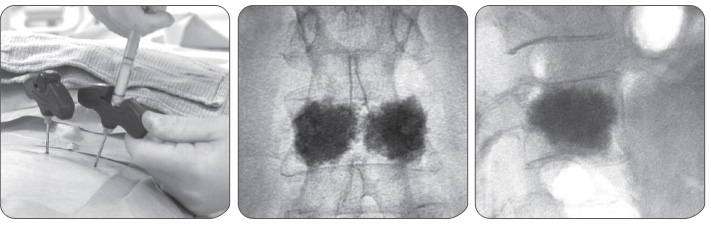

경피적 척추 성형술의 과정

1. 복와위 자세에서 국소마취를 시행 (※ 복와위 : 사지를 구부려서 복부를 땅에 붙이고 목을 세운 자세)

2. X-ray 투시경 하에 척추 천자침을 척추체로 삽입

3. 골시멘트를 주사

4. 수술 시간은 30분 내외 소요, 수술 후 보조기 착용 필수